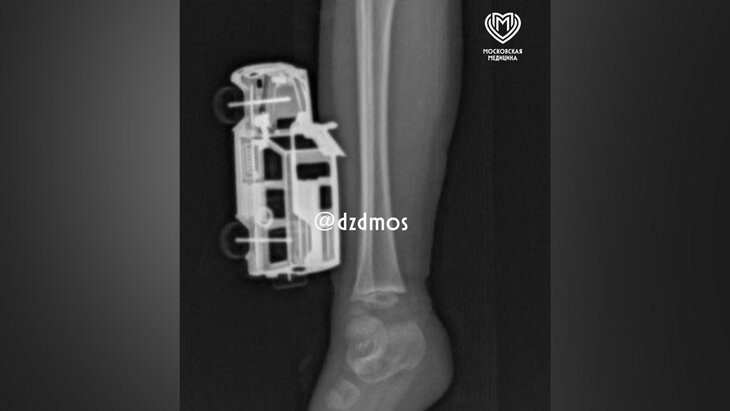

Фото: телеграм-канал "Московская медицина"

Врачи в Москве спасли 4-летнего ребенка, у которого в ноге застряла металлическая игрушечная машинка в голени, рассказали в телеграм-канале Депздрава столицы.

По словам родителей, ребенок прыгнул с кровати и неудачно приземлился на игрушку. Она повредила мягкие ткани правой голени, а части игрушки вошли до подкожножировой клетчатки. Родители вызвали скорую помощь, и ребенка госпитализировали в больницу Сперанского.

Травматолог-ортопед отделения экстренной хирургической помощи Магомед Шихахмедов рассказал, что мальчику сделали рентгенографию, так как нужно было исключить повреждения костей и понять, насколько глубокие повреждения.

После этого игрушку удалили и выполнили хирургическую обработку раны. Уже через сутки мальчика выписали домой под амбулаторное наблюдение.